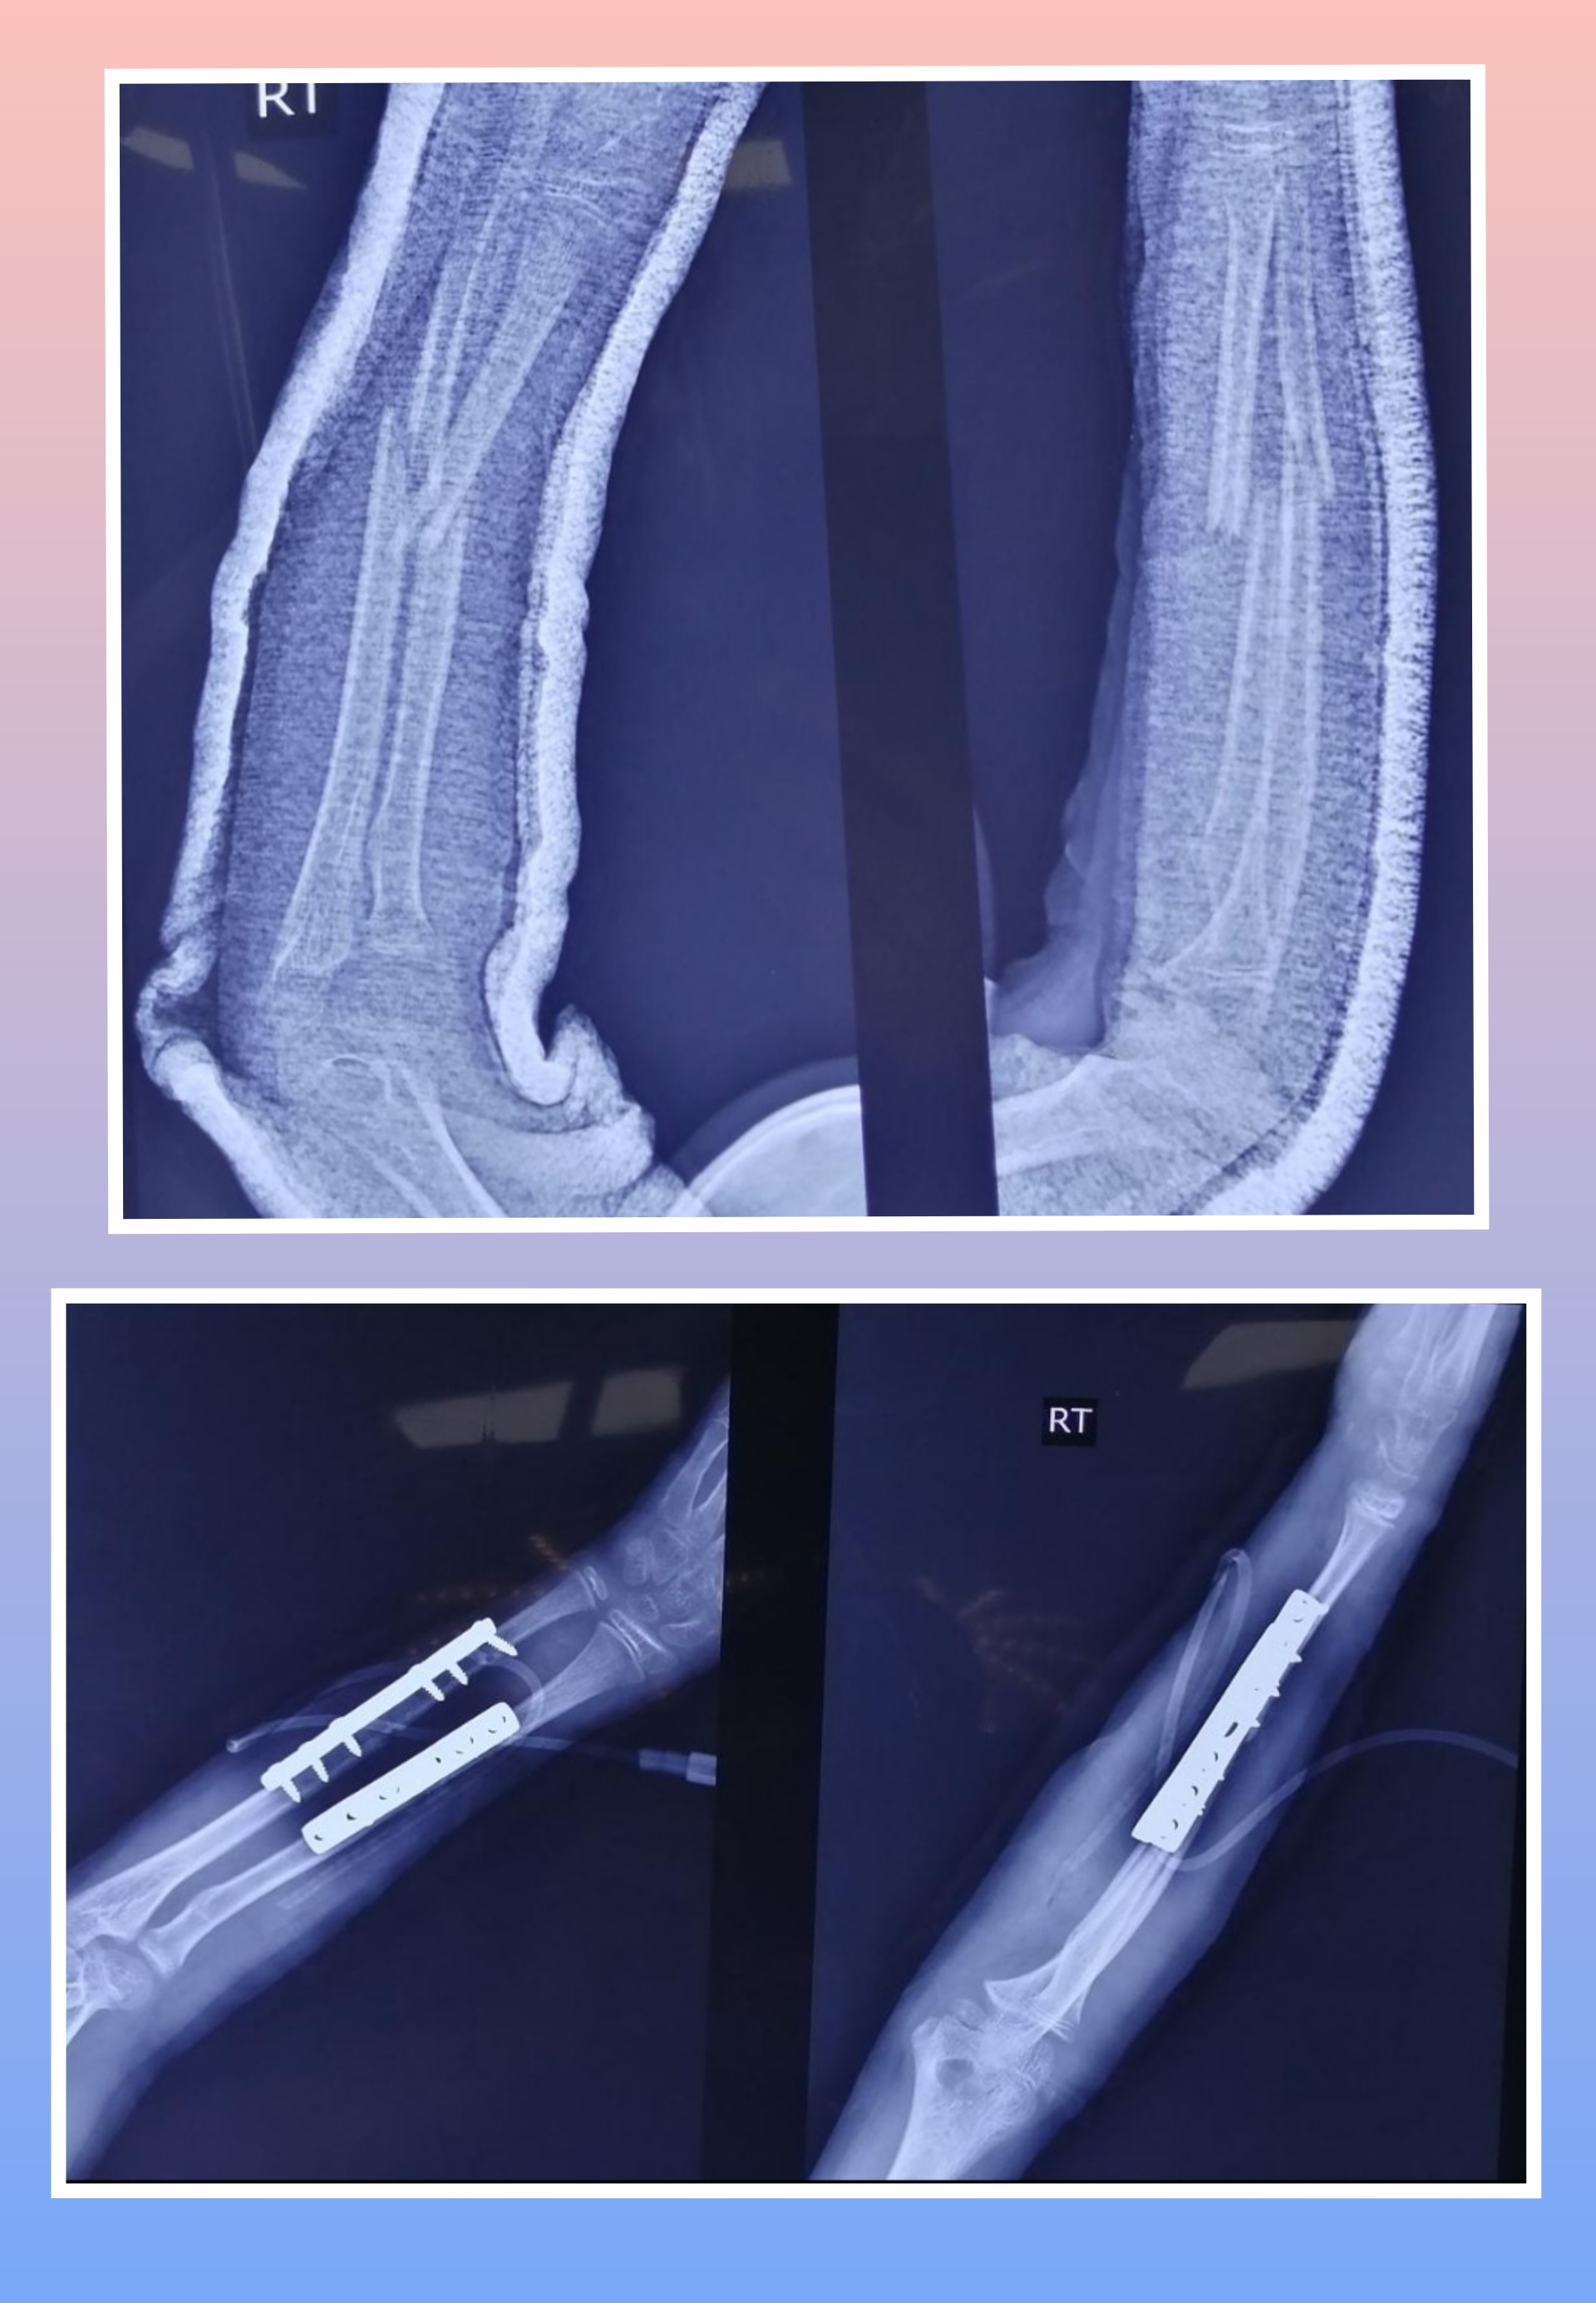

Warning: Graphic Content

The following section contains graphic images of surgical procedures. These images are intended for educational purposes and may be disturbing to some viewers. Viewer discretion is advised.

Surgeries